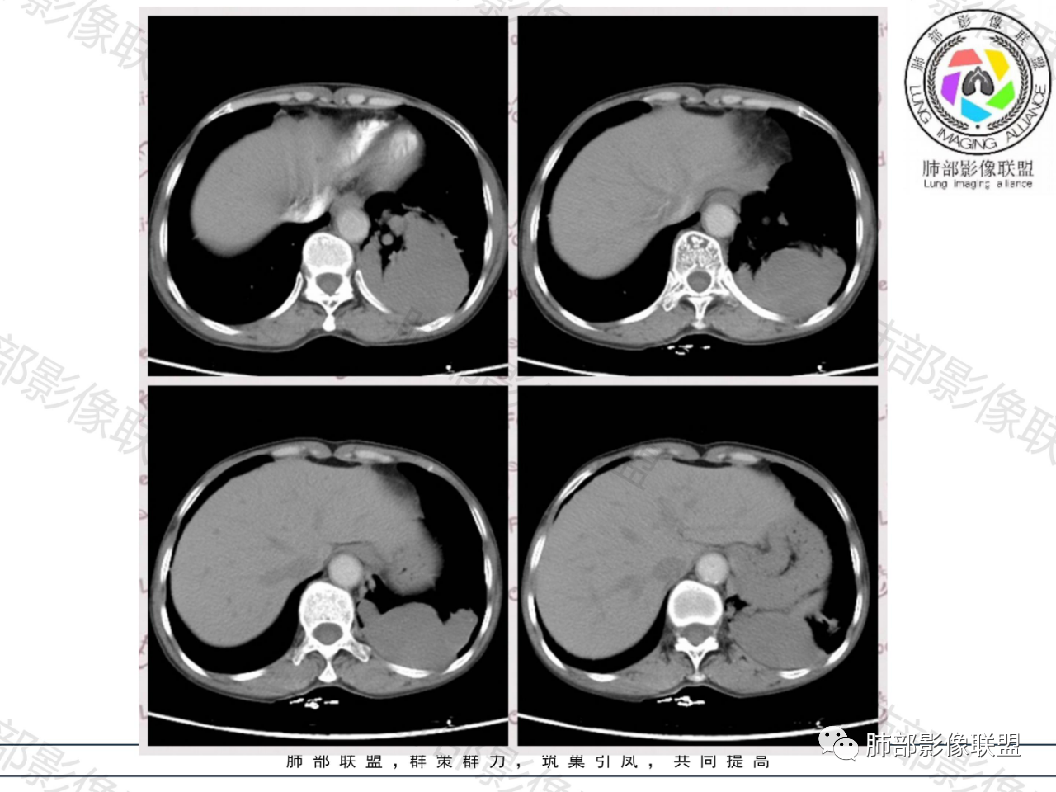

晨读:左肺下叶实性肿块,边缘光滑膨隆,近端支气管堵塞,远端宽基底与胸膜相连,部分胸膜下间隙消失,大肿块周围伴有多发小结节,小结节边缘光滑,平扫密度均匀,增强后不均匀强化,部分可见富血供强化,右肺下叶胸膜下条形实变影,收缩,右肺可能炎性病变,左肺下叶恶性肿瘤(癌肉瘤,肉瘤,鳞癌)

左肺下叶多发囊性病灶,有相通融合,有分隔线,增强无明显强化,考虑囊肿类病变

中年女性,体检发现左下肺占位,囊性为主,增强扫描大部分无强化,仅有局部边缘强化,似见内部分隔,可能为支气管壁,边缘有散在小结节,强化一致。

晨读病例,中年女性,体检发现病灶,左肺下叶多发囊性病灶,部分相通融合,内有分隔线,边界清晰,增强病灶无明显强化,考虑支气管囊肿或闭锁,神经节细胞瘤,其次感染性病变(结核)。

老年女性,查体发现,无症状,左肺下叶大肿块周围有同样小病灶,密度低,有包膜,多发囊样,内部无明显强化,周围轻度强化,支气管推移有狭窄,周围肺组织挤压,与胸膜宽基底相连,长轴与胸膜平行,考虑来源胸膜,SFT应该不均匀强化,考虑神经源性肿瘤,鞘瘤?鉴别SFT,肺隔离症,神经内分泌肿瘤等。

晨读:中年女性患者,无症状体检发现,胸部CT:左下肺外后基底段胸膜下不规则病灶,内部密度均匀,边缘部分光滑,部分分叶,呈膨胀性生长,增强扫描无强化,支气管血管显示不清,冠状位与脊柱的关系似D字征,综合考虑良性病变:

左肺下叶胸膜下囊性肿块,其内见分隔,囊壁强化,周围多个小囊性病灶,周围肺组织无气肿,考虑1支气管囊肿或闭锁2CCAM

晨读:左肺下叶囊性肿块,边缘光滑膨隆,近端支气管堵塞,临近肺呈受压改变,与胸膜平行,近端多发小结节,小结节边缘光滑,似见轻度强化,血管贴边,内见分隔,考虑良性病变,支气管源性囊肿,结核或隐球

晨读:中年女性,无症状。胸部CT:左下肺后基底段肿块样病灶,边界清楚,患侧肺体积有减小。边缘光滑,囊性为主,可见分隔,相应肺段支气管未见,邻近肺受压,增强扫描强化不明显,仅有局部边缘强化,可能为支气管壁。个别层面似有肺外血管穿入。周围有散在小结节,形态、边缘、密度、强化一致。右下叶前基底段索条影。

考虑:支气管囊肿>肺隔离>CPAM>TB,鉴别Ca。

中年女性,左下肺占位,以囊性为主,增强扫描大部分无强化,仅有局部边缘强化,内部似见分隔,边缘有散在小结节,强化一致;考虑良性病变,1.支气管囊肿?2.左肺下叶肺隔离症?3.隐球菌感染?4.右肺中叶内侧段慢性炎症。